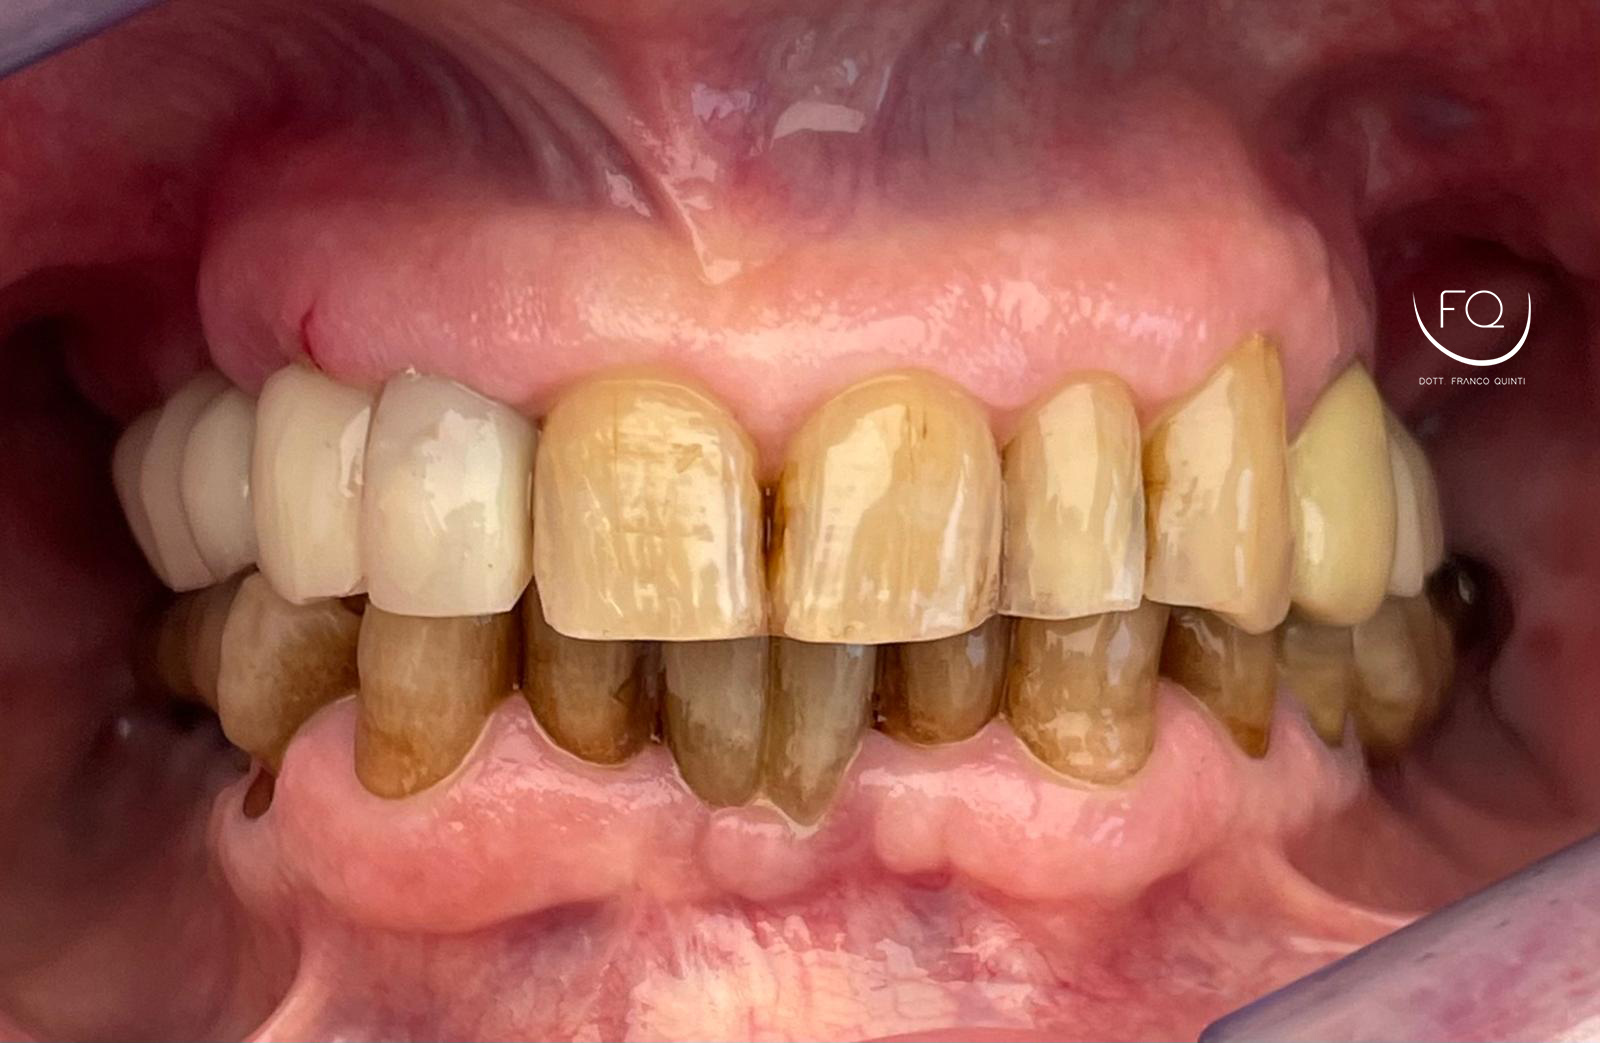

Nell’intervento sono stati inseriti 6 impianti PRAMA di Sweden & Martina con contestuale esecuzione del carico immediato.

Ciò significa che, appena terminata la chirurgia, sono stati applicati anche i denti provvisori.